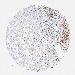

PANCREATIC CANCER - Protein expressioni

A mouse-over function shows sample information and annotation data. Click on an image to view it in a full screen mode. Samples can be filtered based on level of antibody staining by selecting one or several of the following categories: high, medium, low and not detected. The assay and annotation is described here.

Note that samples used for immunohistochemistry by the Human Protein Atlas do not correspond to samples in the TCGA dataset.

Antibody stainingi

Antibody staining in the annotated cell types in the current human tissue is reported as not detected, low, medium, or high, based on conventional immunohistochemistry profiling in selected tissues. This score is based on the combination of the staining intensity and fraction of stained cells.

Each image is clickable and will lead to virtual microscopy that enables deeper exploration of all samples and also displays staining intensity scores, fraction scores and subcellular localization as well as patient and tissue information for each sample.

Antibody HPA028814

Antibody CAB004322

Staining

High

Medium

Low

Not detected

Intensity

Strong

Moderate

Weak

Negative

Quantity

>75%

75%-25%

<25%

None

Location

Nuclear

Cytoplasmic/membranous

Cytoplasmic/membranous,nuclear

Adenocarcinoma, NOS

Adenocarcinoma, metastatic, NOS